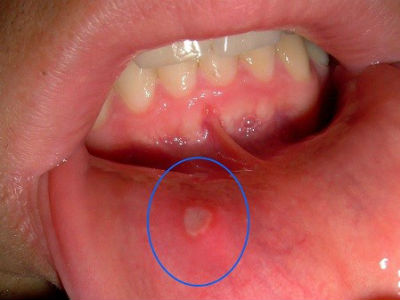

7 loại vitamin tàn phá cơ thể nếu dùng quá liều

Ngày càng có nhiều người quan tâm đến sức khỏe của mình và luôn bổ sung đầy đủ chất dinh dưỡng mỗi ngày, cũng như các loại vitamin. Tuy nhiên, bổ sung quá nhiều một số loại vitamin dưới đây có thể sẽ ảnh hưởng không tốt đến sức khỏe.